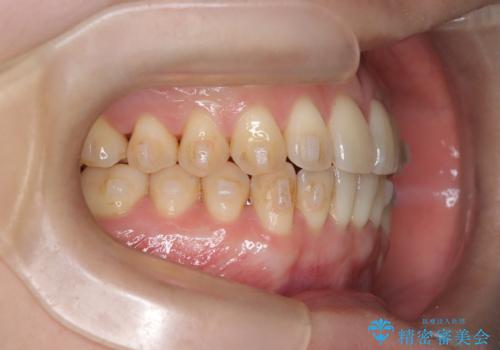

- 「下の前歯が斜めになっている」を主訴に来院された患者様です。

下顎前歯に叢生があり、右上2は反対咬合の状態でした。

下顎前歯の叢生がとれ右上2の反対咬合も改善し患者様にも満足していただけました。治療期間は1年~1年半を見込んでいましたが、患者様の協力もあり10か月で矯正を終えることが出来ました。